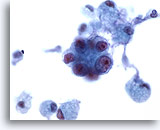

Figure 105

Bronchial wash

The cells of well and moderately-differentiated pulmonary adenocarcinoma are typically clustered. 20x